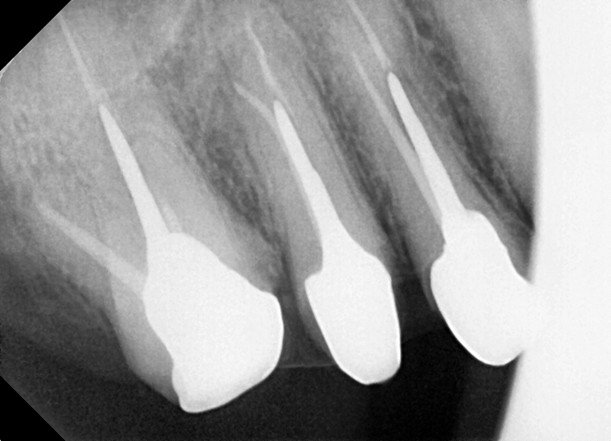

1. Endodontic Foundation (Root Canal Treatment)

The treatment began with a successful root canal procedure. The canal was carefully prepared to receive a custom post while maintaining a 4–5 mm apical seal to ensure long-term success.

2. Custom Cast Post & Core Fabrication

A custom cast post was designed to fit precisely within the root canal.

The case was diagnosed as severely compromised dentition due to extensive caries, requiring reinforcement through advanced prosthodontic techniques to restore both structure and function.